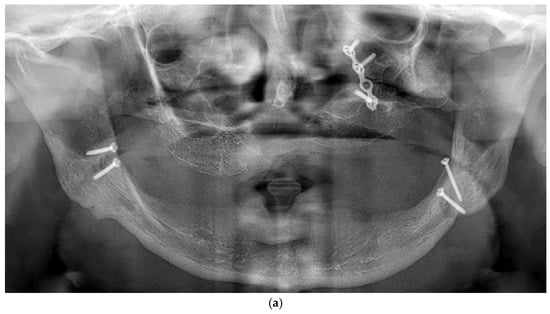

Figure 5.

(a) A panoramic radiograph of the patient after subperiosteal implants placement. (b) Intraoral picture of the mandible following subperiosteal implant placement.